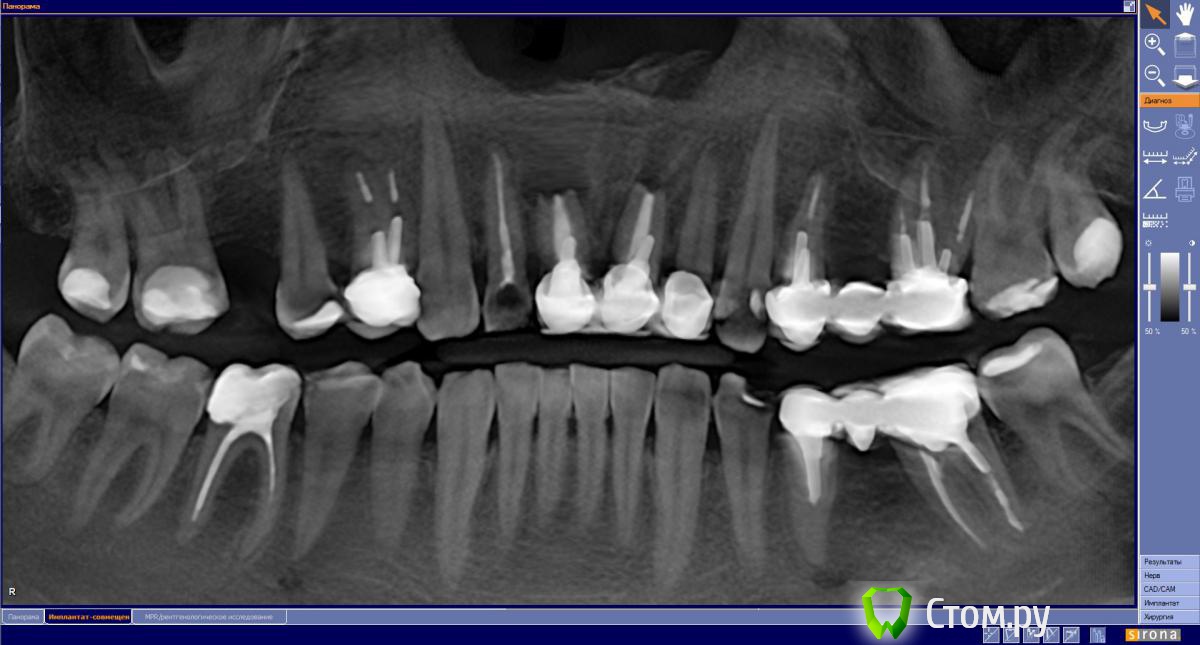

Sergei27 Опубликовано 31 августа, 2014 Поделиться Опубликовано 31 августа, 2014 В полости рта после жесткой пищи напротив зуба 4,6 возникаем мешочек 5мм. При надавливании лопается, ранка заживает, было уже 3 раза примерно 90, 60 и 25 дней назад. Что это, киста? Можно ли пере лечить канал или удалять зуб? Ссылка на комментарий

Sergei27 Опубликовано 19 сентября, 2014 Автор Поделиться Опубликовано 19 сентября, 2014 ПерелечиватьКанал до конца пройти не удается, склерозировал. Еще 5 мм. Наверное надо удалять Ссылка на комментарий